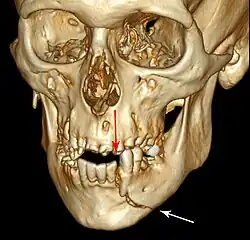

Injuries to supporting bone

This injury involves the alveolar bone and may extend beyond the alveolus.[5][6] There are five different types of alveolar fractures:

- Communicated fracture of the socket wall

- Fracture of the socket wall

- Dentoalveolar fracture (segmental)

- Fracture of the maxilla: Le Fort fracture, zygomatic fracture, orbital blowout

- Fracture of the mandible

Trauma injuries involving the alveolus can be complicated as it does not happen in isolation, very often presents along with other types of tooth tissue injuries.

Signs of dentoalveolar fracture:

- Change to occlusion

- Multiple teeth moving together as a segment and are normally displaced

- Bruising of attached gingivae

- Gingivae across the fracture line often lacerated

Investigation: Require more than one radiographic view to identify the fracture line.

Treatment: Reposition displaced teeth under local anaesthetic and stabilise the mobile segment with a splint for 4 weeks, suture any soft tissue lacerations.